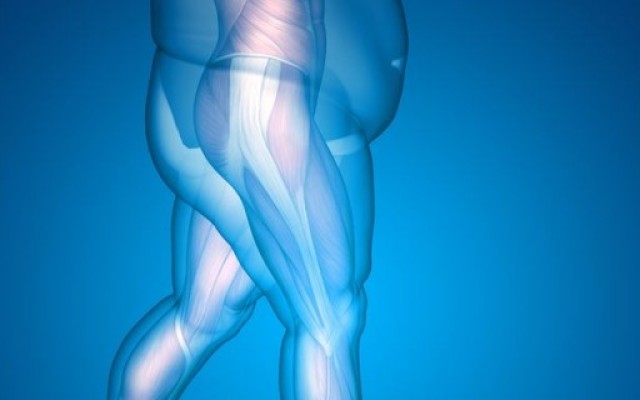

Smoking and Obesity are the major risk factors

Like training for a marathon, ‘training’ for surgery by getting your body in better shape may lessen the risk of complications during your surgery and improve your post-surgery recovery.

Obesity is major problem facing our affluent society. In 2014-2015, a staggering 63.4 percent of Australian adults were overweight or obese -- well over half of our nation's population. That's almost two in three adults. This is an increase from 1995, which was 56.3 percent, illustrating that the problem is getting worse.

Orthopaedic surgery deals with the treatment...